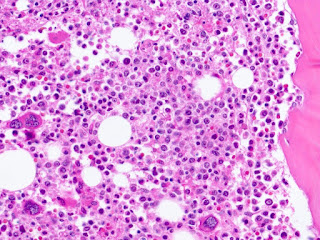

The findings by a University at Buffalo team reveal that activation of a specific transcription factor induces in adult stem cells a phenomenon called pathological quiescence, a situation in which the adult stem cells are rendered incapable of responding to injury by producing myelin-forming oligodendrocytes. The failure to remyelinate is the key feature of MS.

The study defines the role of the previously undescribed transcription factor known as PRRX1 in human oligodendrocyte progenitor cells, the cells that generate myelin-forming oligodendrocytes. The research demonstrated that PRRX1 expression results in the cell cycle arrest and quiescence of oligodendrocyte progenitors, which disabled the production of myelin.

In an animal model of leukodystrophy, the group of genetic disorders in which myelin fails to form or is destroyed in children, the researchers said that pathological quiescence induced by PRRX1 prevented cell colonization of white matter and effective myelin regeneration by transplanted human oligodendrocyte progenitors. They also found that blocking expression of this transcription factor prevented the negative effects of proinflammatory cytokines, such as interferon-γ, which regulates its expression.